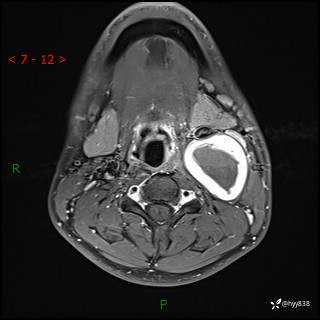

年轻小伙,发现左侧颈部肿物3年余,逐渐增大---结果公布~

现病史:患者约3年前因感冒发现左侧颈部长一肿物,约半个鸡蛋大小,无明显疼痛及其他不适,一直未行特殊处理。3个月前发现左侧颈部肿物变大,随后至当地市第二人民医院耳鼻喉科行左侧颈部彩超示:左侧颈部囊实混合性包块;喉部MPR示:左侧胸锁乳突肌内前方占位,累及左侧喉旁间隙,建议增强扫描。建议手术治疗。患者考虑。随后至我院肿瘤科就诊,行细胞学穿刺示:考虑血管源性肿瘤可能,建议进一步检查。建议至我院口腔科就诊,行颌面部MRI示:左侧颌下腺后方团状异常信号灶,建议增强。建议手术治疗。为求进一步治疗,门诊以“左侧颈部肿物”收入院。 起病以来,患者神志清、精神良好,饮食睡眠良好,大小便正常,体重未见明显变化。

颈部MRI平扫+增强